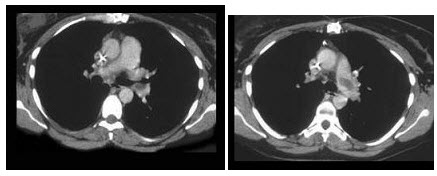

女,64岁,发热、咳嗽1周。胸部CT扫描如下图。

患者抗炎治疗2周后,行胸部CT增强扫描检查,如下图,则最具诊断意义的征象为()

A.多发钙化灶

B.多发含气囊腔

C.多发短毛刺

D.供血动脉起自降主动脉

E.供血动脉起自腹主动脉